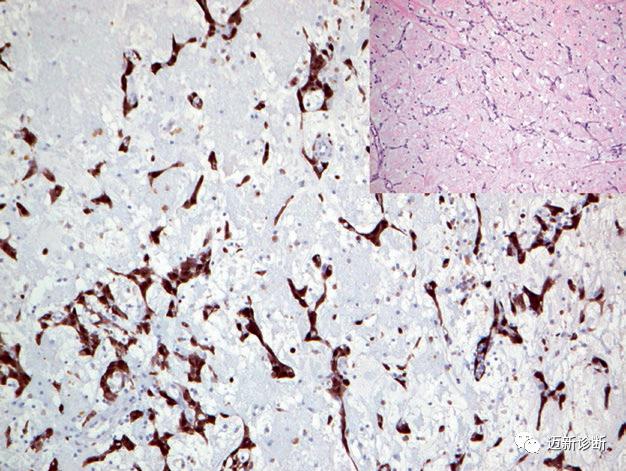

图6. 心脏乳头状弹力纤维瘤,血管内皮细胞免疫组化CD31阳性。

图7. 心脏黏液瘤,肿瘤细胞强阳性表达calretinin。